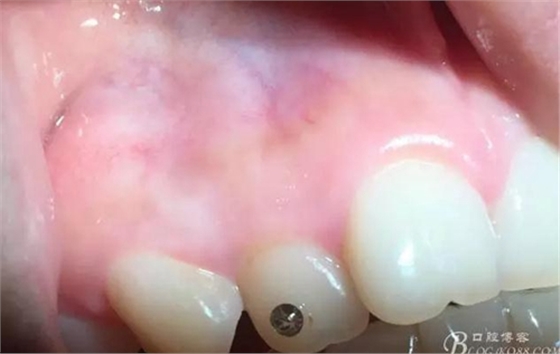

術(shù)后5日

術(shù)后15日

術(shù)后一年

感受:有明確來源性的外源性牙齦色素沉著傳統(tǒng)治療方法有用金剛砂車針磨除著色區(qū)域上皮,或手術(shù)去除著色上皮,或用高頻電刀清除著色上皮,術(shù)后效果無明確預(yù)期,術(shù)中需麻醉,術(shù)后反應(yīng)較大。

激光進(jìn)行牙齦脫色,操作簡(jiǎn)單,效率較高,無需麻醉,患者術(shù)中術(shù)后幾乎無不適反應(yīng),有明確預(yù)期效果。